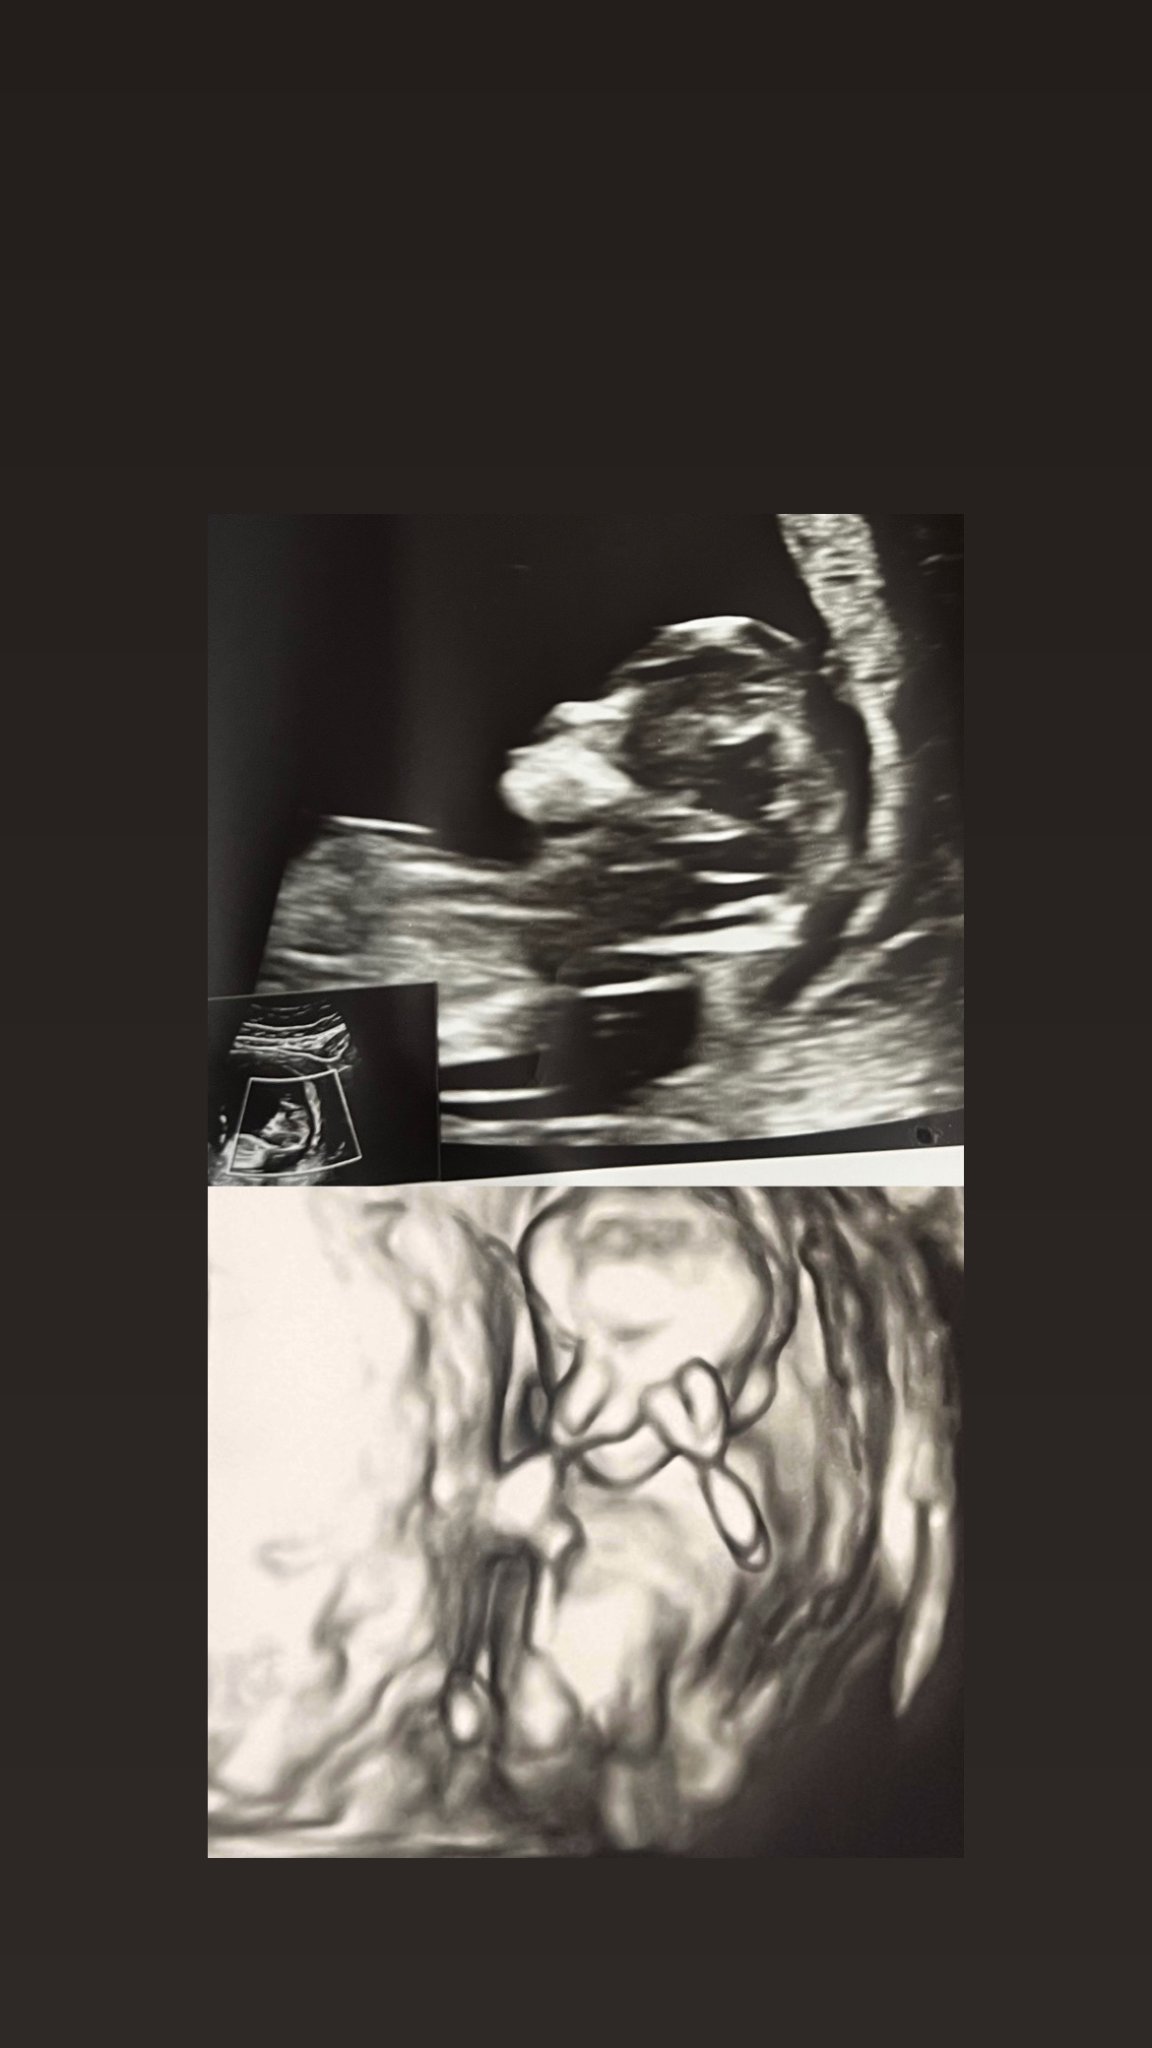

Според вас момче ли е или момиче

Има теория (не научно доказана, по-скоро спекулативна Grinning ), според която може да се предполага полът на бебето според формата на черепа.

Цитирам:

Теорията за черепа (skull theory) е метод за предсказване на пола на бебето чрез анализ на формата на черепа от ултразвуково изображение. Според нея, се предполага, че момчетата имат по-големи, "квадратни" черепи и по-изразени черти, докато момичетата имат по-малки, "закръглени" черепи и по-вертикални чела.

След като се вижда, че черепът е по-ясно изразен, също залагам на момче.

Разбира се, толкова рано единствено пренатален тест би доказал на 100%,

В 10 - 12 гестационна седмица може само да се предполага, все пак теорията с черепите си остава само теория. И при нас ехографските снимки изглеждаха по същия начин. Няма да казвам пола, но предположенията бяха "верни" чак когато направихме пренаталния.

Момче е и се вижда от самолет. На нас в 11 г.с. ни казаха за пола и пренаталния го потвърди.

Как точно "се вижда от самолет", при положение че дори лекарят не е направил никакво предположение? А тук коментиращите веднага определиха пола, без да имат необходимото медицинско образование, и то още в начална гестационна седмица.